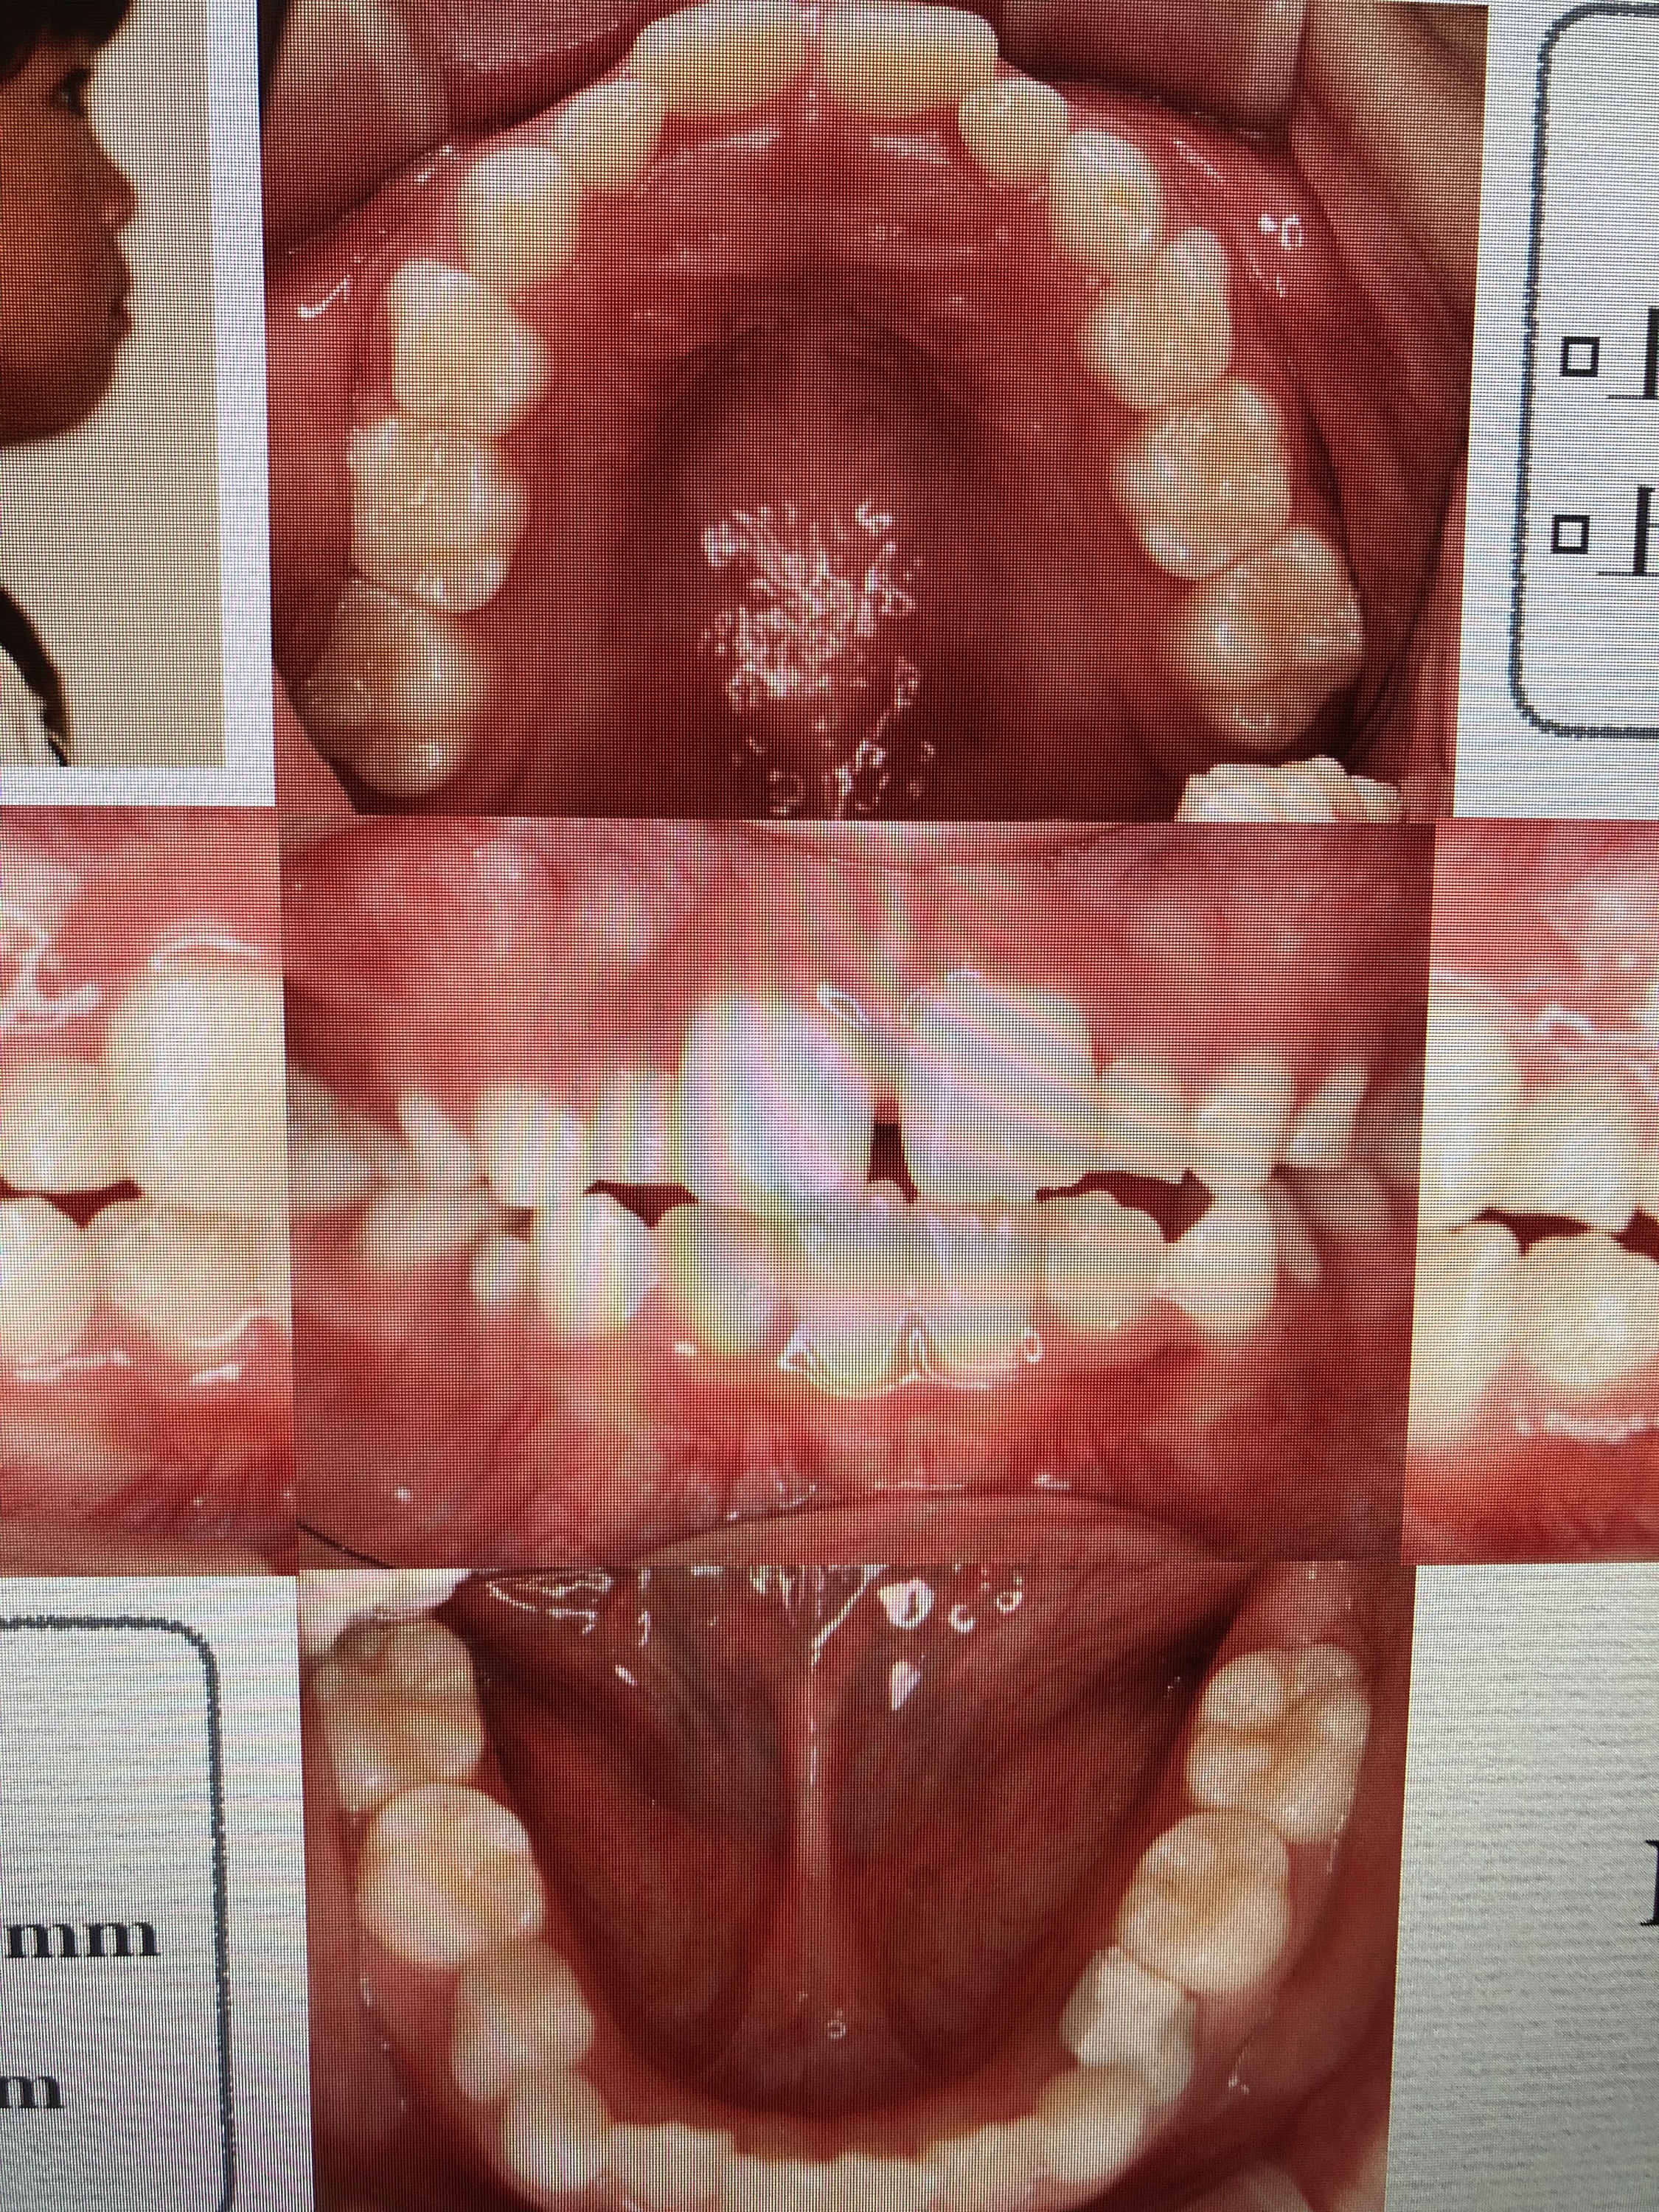

また、当院のMRC担当でも有ります、衛生士からも症例発表をさせて頂きました。小児の健康や歯並びの改善を目的とするMRCシステムを取り入れて、約2年ほどが経ちました。今では、多くの子供達が健全な口腔環境、成長を目的に当院に来院される様になりました。

健全な口腔環境を整える上では、呼吸のバランスや舌の位置、口腔周囲の筋肉の使い方などを日々のトレーニング(アクティビティー)によって正常な状態に改善する事は必要不可欠です。

日頃何気なく行っている’癖’が、良い習慣に変化出来る事で、口腔内の環境は劇的に変化して行きます。当院で行なったMRCの症例写真が物語っていると思います。